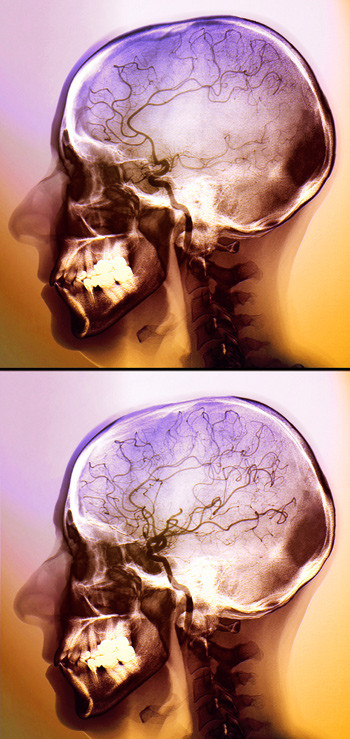

Behandling med trombektomi ved hjerneslag kan gi bedre funksjon enn trombolytisk behandling alene. Dette viser to nye studier.

Illustrasjonsfoto: Science Photo Library

Trombektomi har lenge hatt en usikker rolle i behandlingen av hjerneslag. I The New England Journal of Medicine ble det i februar publisert to studier som viser at trombektomi kan gi hjerneslagpasienter et bedre funksjonsnivå enn trombolytisk behandling alene (1, 2).

I begge studiene ble pasienter med hjerneinfarkt og okklusjon av proksimale kar, påvist ved CT-angiografi, randomisert til trombolytisk behandling eller slik behandling kombinert med trombektomi. Etter 90 dager hadde pasientene som fikk trombektomi et signifikant bedre funksjonsnivå enn pasientene som kun fikk trombolytisk behandling. Det var ingen forskjell i symptomgivende hjerneblødninger mellom de to gruppene. I én av studiene var trombektomi også assosiert med redusert mortalitet (10,4 % versus 19,0 %) (1).